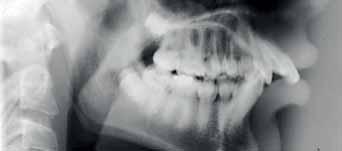

The Dental Panoramic Tomogram (DPT) confirmed the presence of all permanent teeth including the developing third molars (Figure 3). Root morphology appeared normal. The upper right central incisor had a root canal filling. The upper standard occlusal

radiograph revealed that the upper right central incisor had an adequate root filling with no periapical area. In the cephalometric assessment (Figure 4), the ANB value of 7° suggested a moderate Class II skeletal pattern. The vertical proportions were within normal values. The upper incisors were proclined at 122° and the lower incisors were of average inclination at 94°. The interincisal angle was reduced at 119°. The lower incisor to APo and the lower lip to E line were within normal limits.